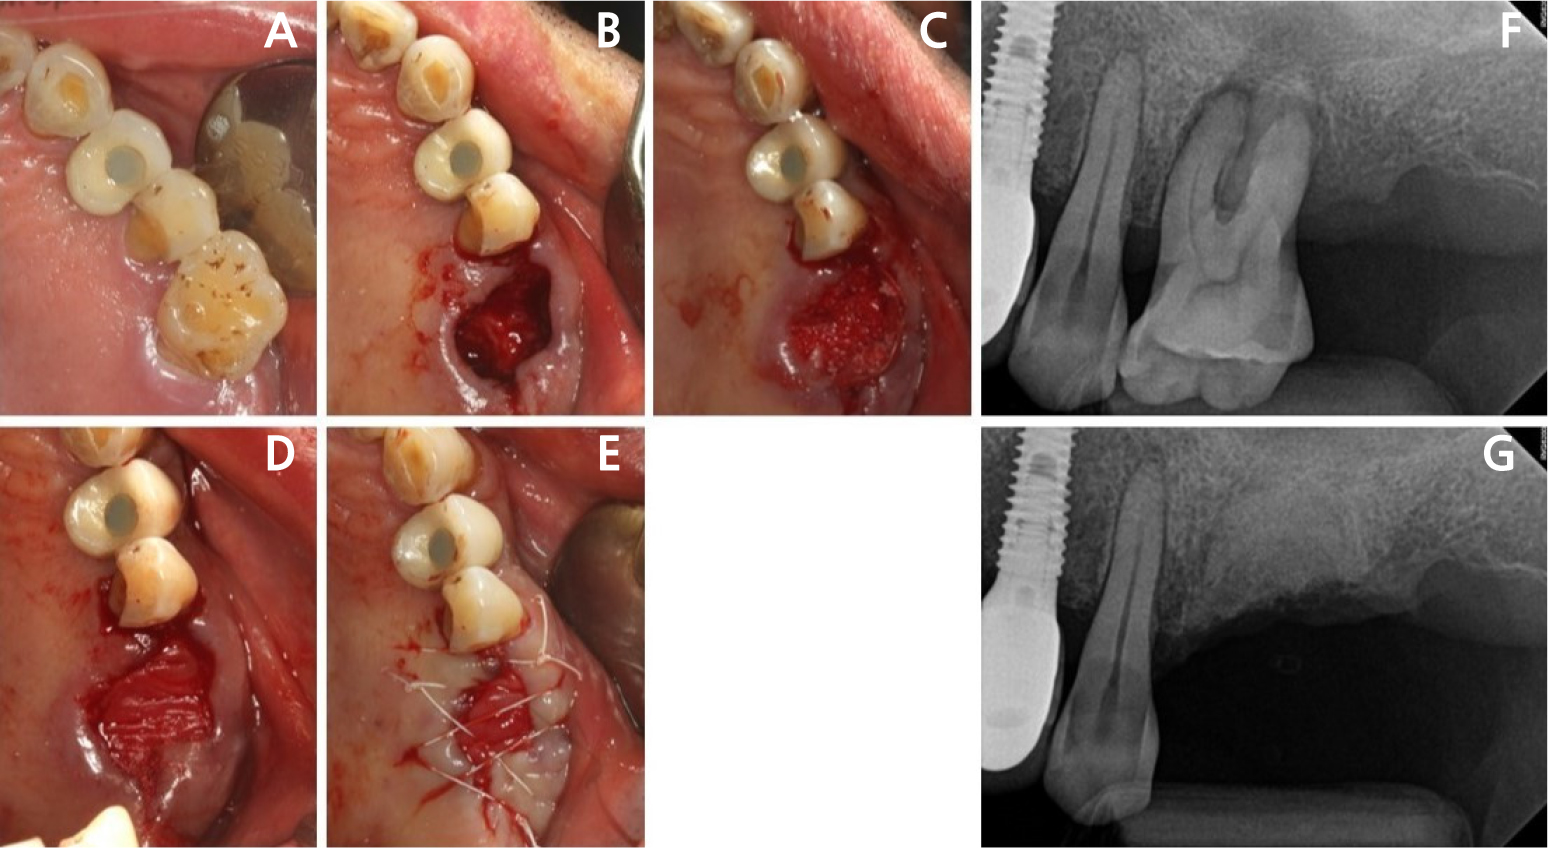

Extractions were performed using elevators and forceps with great care. After extraction, sockets were carefully debrided to remove all granulation tissue. The extraction sockets were then filled with deproteinized porcine bone mineral with 10% collagen (Legograft®; Purgo), without flap elevation, and covered with a collagen membrane of Remaix™ (Matricel GmbH, Herzogenrath, Germany) or Ossix Plus® (Datum Dental Biotech, Telrad, Israel). Primary wound closure was not attempted. The ARP site was stabilized using a 4–0 non-absorbable polytetrafluoroethylene monofilament (Biotex; Purgo) with interrupted and hidden X sutures (Fig. 2). Patients were instructed to rinse twice daily with a chlorhexidine gluconate solution and were prescribed analgesics and antibiotics for 5 days. All patients were followed up 7 to 10 days after the procedure for the removal of suture materials.

Fig. 2

Representative intraoral photographs and periapical radiographs. The severely damaged maxillary first molar (A) underwent ARP (B, C). The grafted site is covered with Remaix (Matricel GmbH, Herzogenrath, Germany) (D) and then sutured (E). (F) and (G) Periapical radiographs obtained before extraction with ARP and immediately after ARP, respectively.